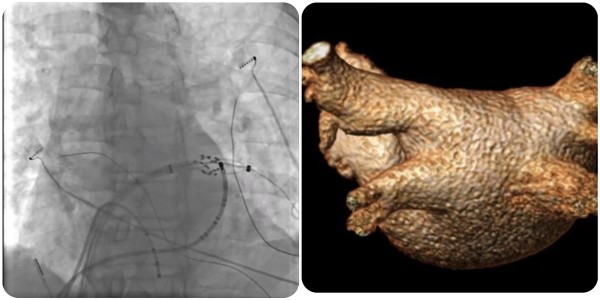

近日,小妲己直播app (简称小妲己直播app )心血管内科团队完成广西首批三维标测系统指导下经皮导管脉冲电场消融术(即CardiPulse脉冲电场消融系统上市后广西首批应用),为一名阵发性房颤患者进行了房颤脉冲电场消融治疗,成功帮助患者恢复正常心律。

在夏文豪的指导下,小妲己直播app 心血管内科心律失常介入团队为患者制定了个性化诊疗方案,并联系介入导管中心、重症医学科、心胸外科、手术麻醉中心做好应急预案,为手术全程保驾护航。手术仅2小时,消融过程中患者心律转为正常,肺静脉即刻隔离,术后恢复良好,目前已康复出院。

脉冲电场消融(Pulsed Field Ablation,PFA)利用短时程、高电压的多个电脉冲释放消融能量,可在细胞膜上产生不可逆的纳米级微孔,导致细胞死亡,可用于房颤导管消融,实现肺静脉隔离。